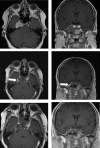

Results: In 22 patients (52,4%) gross total resection was achieved according to the final IO-MRI. In 20 patients (47,6%) complete tumor removal was not possible because of extension to the petrous bone (8 patients), pontocerebellar angle (6 patients), prepontine cistern (4 patients), temporobasal (1 patient), cervical axis (1 patient). In 13 patients, the surgery was continued after the first IO-MRI control was performed, which showed a resectable residual tumor. 7 of these patients achieved total resection according to the second IO-MRI, in the other 6 patients all efforts were made to ensure maximal resection of the tumor as much as possible without morbidity. Repeated IO-MRI helped achieve gross total resection in 7 patients (53.8%).

Conclusions: Our study proves that the use of IO-MRI is a safe method that provides the opportunity to show the degree of resection in skull base chordomas and to evaluate the volume and location of the residual tumor intraoperatively. Hence IO-MRI can improve the life expectancy of patients because it provides an opportunity for both gross total resection and maximal safe resection in cases where total resection is not possible.